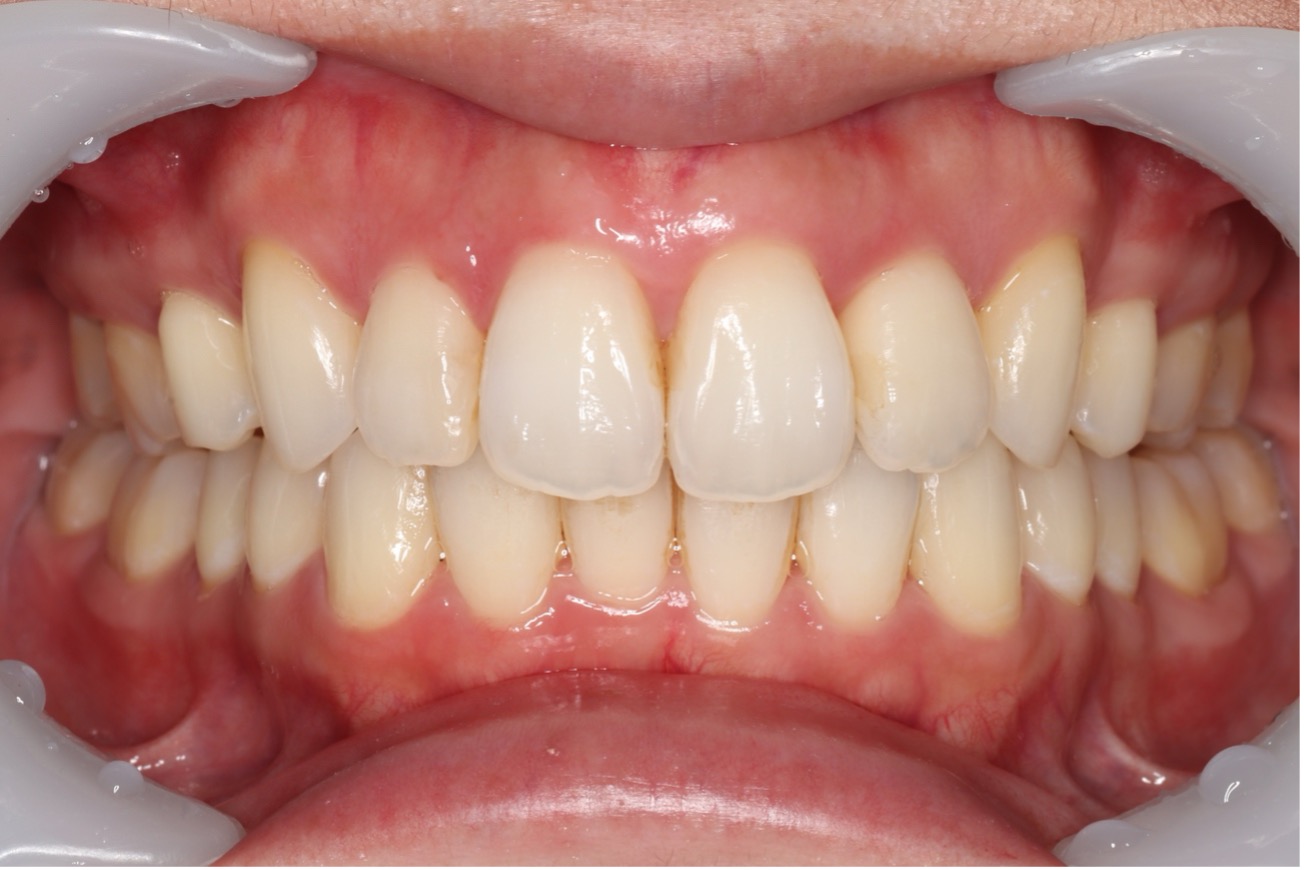

歯と歯の間に隙間がある状態です。

食事のときにうまく噛みきれなかったり、食べ物が歯に詰まりやすくなるなどのデメリットの他に、歯と歯の間から空気が抜けることで、発音にも支障が出るケースもあります。